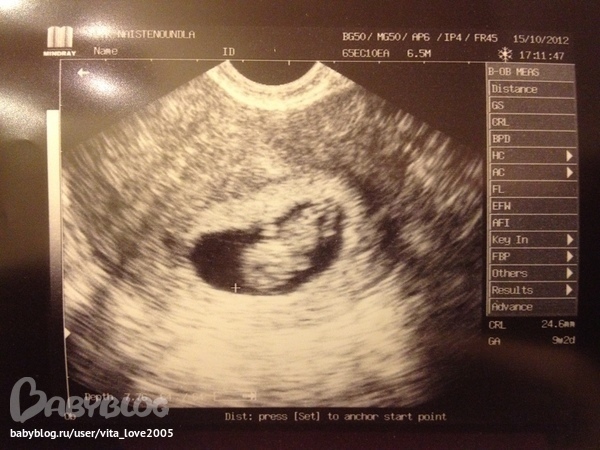

9 недель и 2 дня